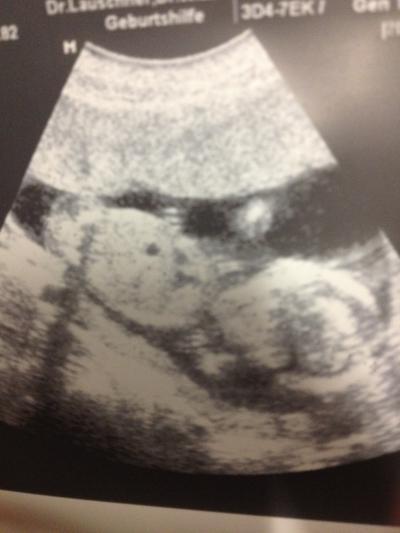

Guten Abend ihr Lieben, bin nun mit vollem Magen wieder zu Hause. War zur Feier des Tages mit Männe noch beim Griechen. Lecker Nun zu meinem Besuch beim FA. Meinem Krümel geht es super, er ist nun schon stolze 10cm groß und genauso entwickelt wie es sein muss, die Ärztin ist jedenfalls hoch zufrieden. Beim nächsten Termin wird auch nicht mehr SSL gemessen sondern Kopf bis Fuß. War so richtig schön ihn wieder zu sehen und das Herz hat doll gebubbert, obwohl Krümelchen diesmal relativ ruhig war und nicht gezappelt hat Tja und eine Tendenz zum Geschlecht gibt es nun auch. Wird aber erst verraten wenn es eindeutig ist Anbei auch ein Bildchen. Finde die Qualität nicht so dolle aber ich hoffe ihr könnt was erkennen. Ist das erste Bauch-Schall-Foto :-) Der schwarze Punkt in der Mitte ist der Magen. Mein nächster Termin ist am 08.03. und die Ärztin meinte bis dahin wird man das Geschlecht auch eindeutig sehen können. 3D-US lassen wir dann so um die 30. Woche machen und das gute ist, man kann es direkt in der Praxis machen da sie so ein Spezialgerät für 3D-Aufnahmen hat. ET bleibt auch beim 02.08. So, ist leider doch bisl länger geworden... Jedenfalls bin ich glücklich und zufrieden und wünsche euch noch einen schönen Abend Grüßle Tina

Wow tolles bild sieht nach bub aus